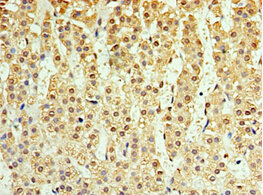

Immunohistochemistry of paraffin-embedded human adrenal gland tissue using CSB-PA875653ESR1HU at dilution of 1:100